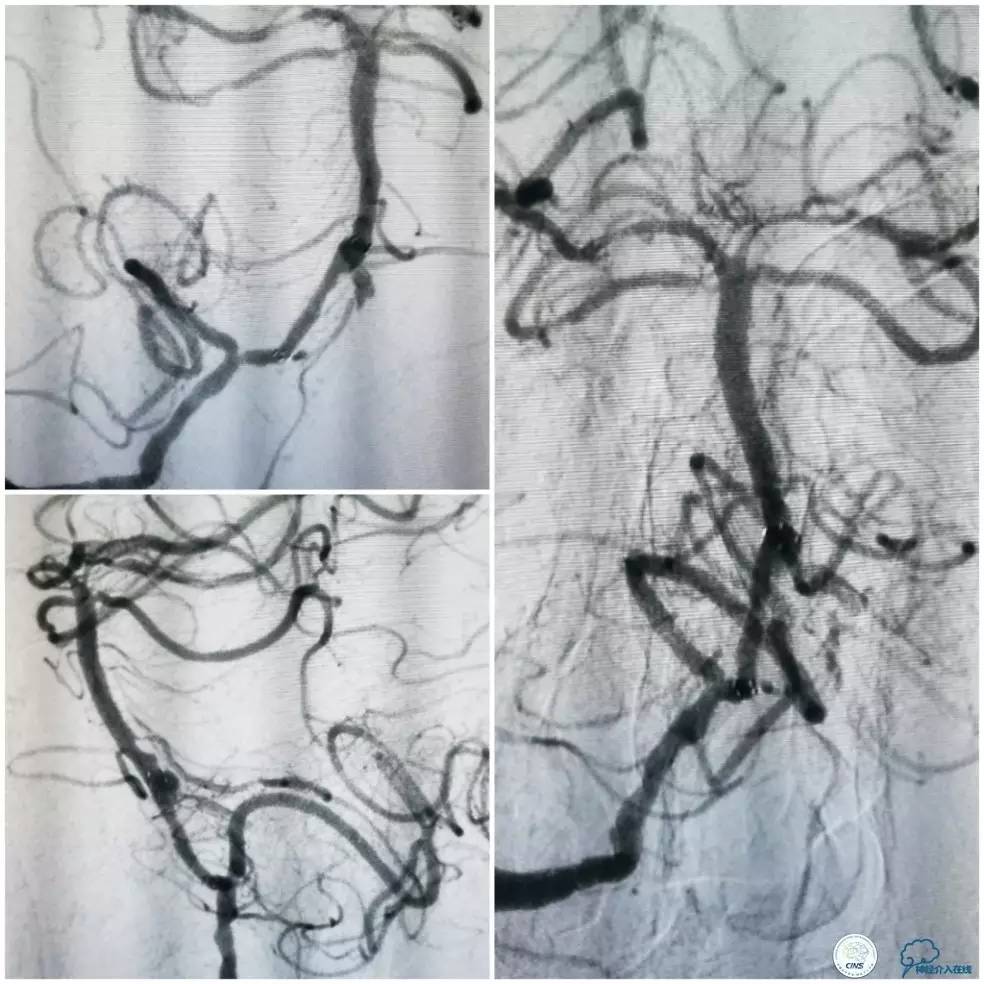

术前DSA:右椎动脉V1段长段重度狭窄,V4-基底动脉交界区显影浅淡,狭窄程度重,但具体程度显示欠佳(图7)。左椎动脉V1段闭塞,左椎动脉V2远段经侧支代偿显影,V3段以远未见显影(图8)。前循环造影未见明显前循环向后循环代偿(图9)。

图7

图8

图9